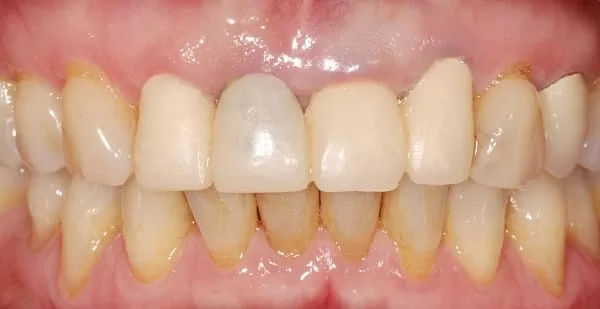

三個月後,四顆門牙裝上3D齒雕牙套,恢復咀嚼功能及美觀;看不出來哪一顆是植牙的牙齒。(圖5,6)

(圖5: 治療後正面觀)